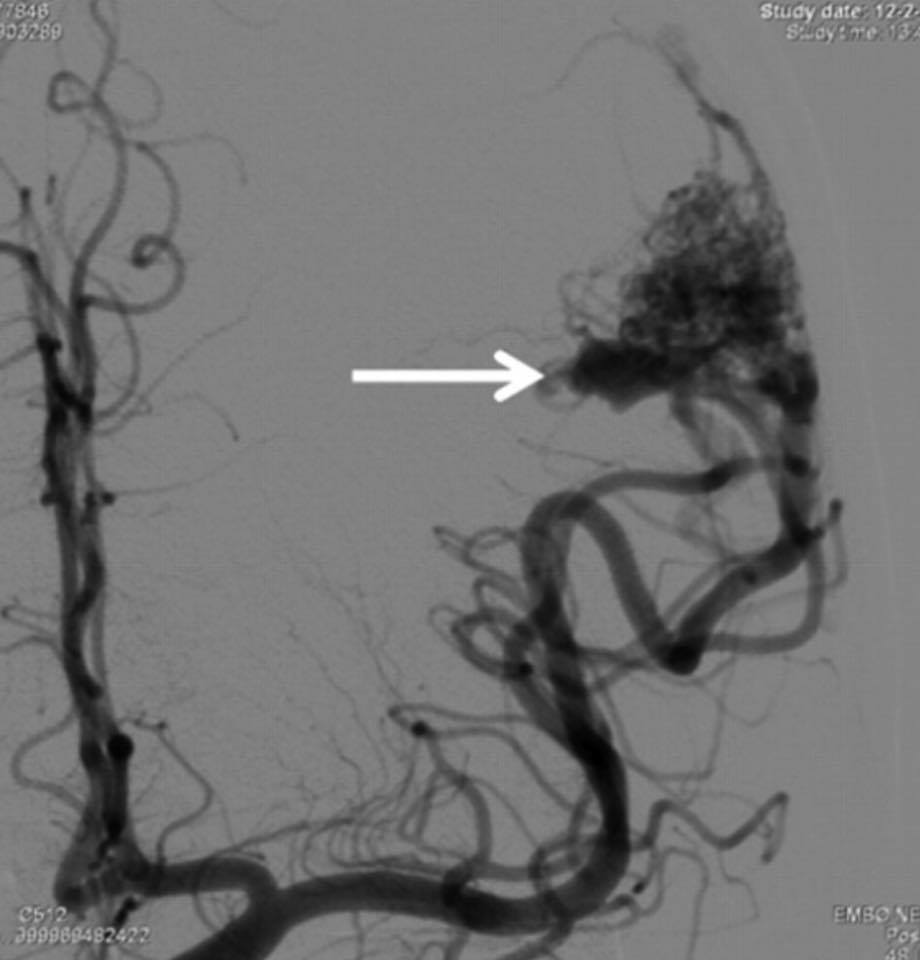

兩天後….在私家醫院為她做診斷式的動態腦血管造影來確定䐉血液的流動模式後,再進行了4 小時的顯微鏡手術….AVM的計時炸彈完全切除……..在AVM旁邊的腦部亦能看到血鐵黃素的舊有殘留血液。手術後兩天出院。